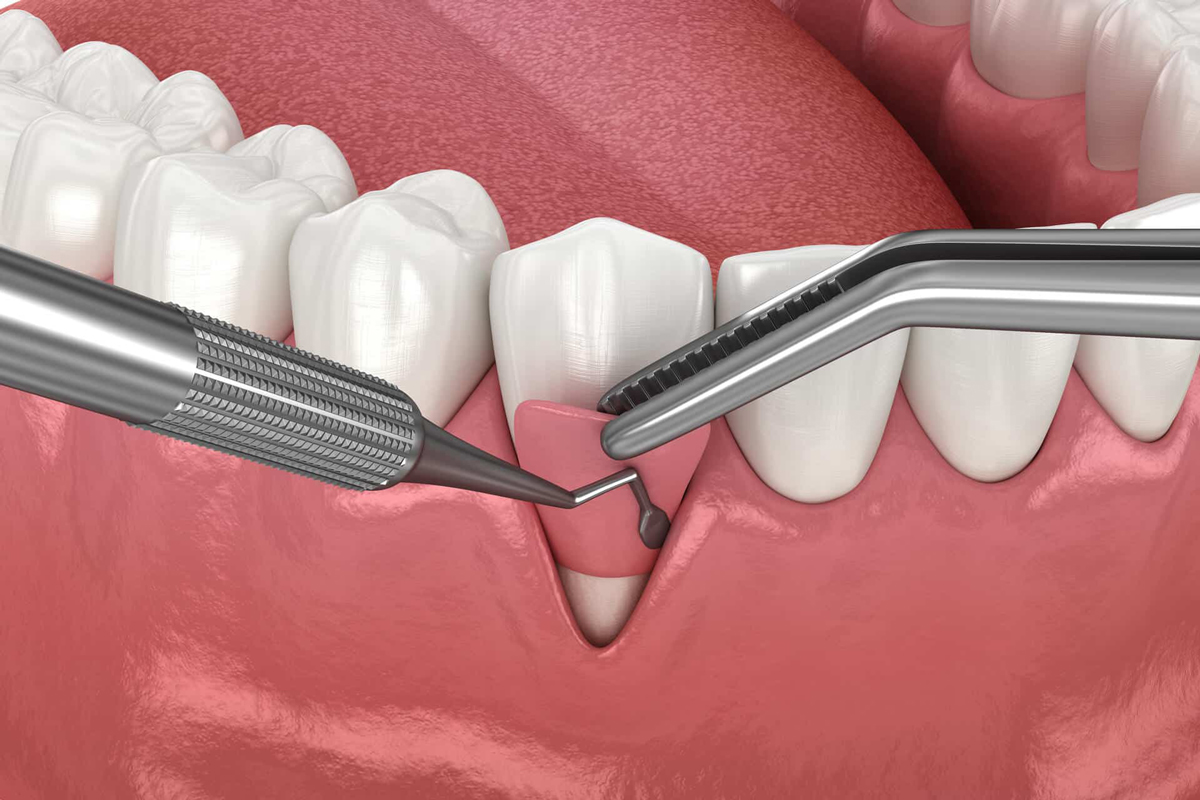

انواع جراحیهای لثه شامل جرمگیری عمیق (Scaling & Root Planing)، پیوند لثه (Gum Graft)، جراحی فلپ (Flap Surgery)، و بازسازی استخوان و بافت (Bone & Tissue Regeneration) میشوند. انتخاب نوع جراحی بسته به شدت بیماری لثه، میزان تحلیل استخوان و شرایط دهان بیمار انجام میگیرد. هدف اصلی این درمانها، کنترل عفونت، حفظ بافت لثه، و بازگرداندن عملکرد و زیبایی لبخند است.

مزایای جراحی لثه فراتر از سلامت دندانهاست؛ این درمان موجب کاهش التهاب، کنترل خونریزی، جلوگیری از بوی بد دهان و حفظ زیبایی لبخند میشود. در بیماران با تحلیل شدید لثه، پیوند لثه میتواند نواحی آسیبدیده را ترمیم کند و از عقبنشینی بیشتر لثه جلوگیری نماید. جراحی فلپ نیز با باز کردن ناحیه اطراف دندان و تمیز کردن عمیق ریشهها، زمینه رشد مجدد بافت و استخوان را فراهم میکند.